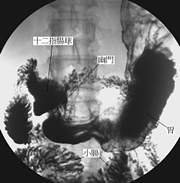

上消化道攝影是一種特殊的x光檢查,其檢查的範圍包括食道、胃、十二指腸以及其他小腸(空腸和迴腸)。

(1)當開始檢查時,會先給一小包蘇打粉,請合著一小杯的開水迅速吞下,此蘇打粉的作用是利用氣體使胃、腸道脹起來 以利觀察黏膜的情形。醫護人員會遞上一杯如奶昔般的腸胃道造影劑(鋇劑),請配合指示飲用,例如請您喝一口含在嘴巴,請您吞下時才可以吞下,檢查過程中檢查台上會開始平躺、俯臥、側躺或翻轉,有時則需要被檢查者配合閉氣,同時以X光視需要做不等次數之照相。只檢查食道、胃及十二指腸者約費時20~30分鐘,若包括空腸和迴腸者約費時2小時以上。